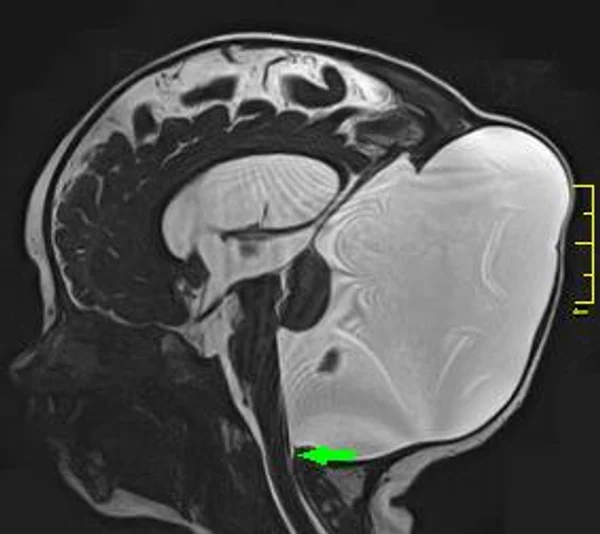

кисты, аномалии Денди-Уокера и др.Операции при внутричерепных кистах. В основном встречаются арахноидальные кисты различных локализаций и кисты сосудистых сплетений боковых желудочков. Пациентам с врождёнными кистами операции проводятся в следующих ситуациях: увеличении объема кисты в динамике, наличии клинических проявлений, компрессии и дислокации мозговых структур, наличии окклюзии ликворных путей. Нами используются 2 способа хирургического лечения кист: эндоскопическая перфорация стенок кист и открытая резекция кист. Открытая резекция кист проводится при ретроцеребеллярных арахноидальных кистах (рис. 2), при арахноидальных кистах межполушарной щели при отсутствии непосредственного контакта их стенок со стенками расширенных желудочков головного мозга и повторного увеличения кист средней черепной ямки после эндоскопической кисто-цистерностомии. Техника операции заключается в проведение краниотомии и максимальном иссечении стенок кист с созданием широкого сообщения кист с субарахноидальным пространством. Эндоскопические операции проводятся при арахноидальных кистах межножковой и пинеальной цистерн, арахноидальных кистах межполушарной щели при тесном контакте их стенок со стенками расширенной желудочковой системы (рис. 3), первично при арахноидальных кистах средней черепной ямки, а также при кистах сосудистых сплетений боковых желудочков. При арахноидальных кистах межножковой цистерны эндоскопически проводится перфорация стенок кисты, сообщая ее с просветом III желудочка и межножковой цистерной – эндоскопическая вентрикуло-кисто-цистерностомия (рис. 4). При арахноидальных кистах пинеальной цистерны проводится перфорация кисты в передне-верхних её отделах с созданием сообщения полости кисты с просветом III желудочка – эндоскопическая кисто-вентрикулостомия. С целью предотвращения облитерации сформированного отверстия иногда в полость кисты под контролем эндоскопа вводится стент перфорированный на протяжении (рис. 5, 6). Эндоскопическая кисто-цистерностомия выполняется при арахноидальных кистах средней черепной ямки. При этом создается широкое сообщение кисты с базальными цистернами. При кистах сосудистых сплетений боковых желудочков проводится их вскрытие в просвет боковых желудочков – эндоскопическая кисто-вентрикулостомия. При множественных кистах проводится их хирургическое сообщение между собой – интеркистосмия